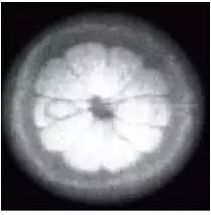

首次头颅 CT 检查

幸运的橙子

扫描仪问世后的第二年,荷兰科学家

罗伯洛赫尔开启对核磁共振的研究并得到放射

学界众所周知的核磁共振图像诺丁汉的橙子

1978年组建了团队开展“质子项目”的研究

并拥有了当时世界上最强大的一台长达1米的

0.15T磁体。1980年12月3号得到了第一幅

人类头部核磁共振图像后来,在优化了

序列设计后,他们又获得了体部图像

放射科医生也第一次看到了可分辨的器官

丁汉的橙子和首次头颅 MR 成像